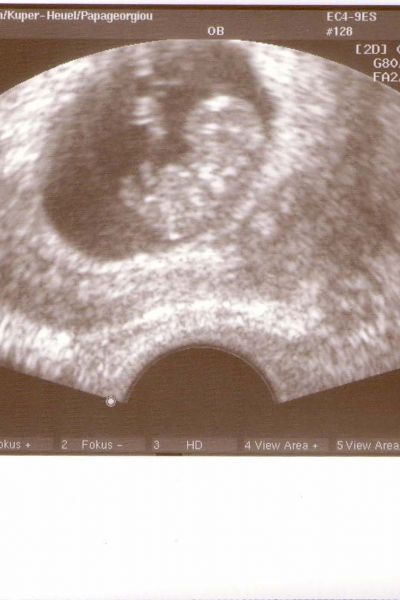

unser würmchen

meine familie